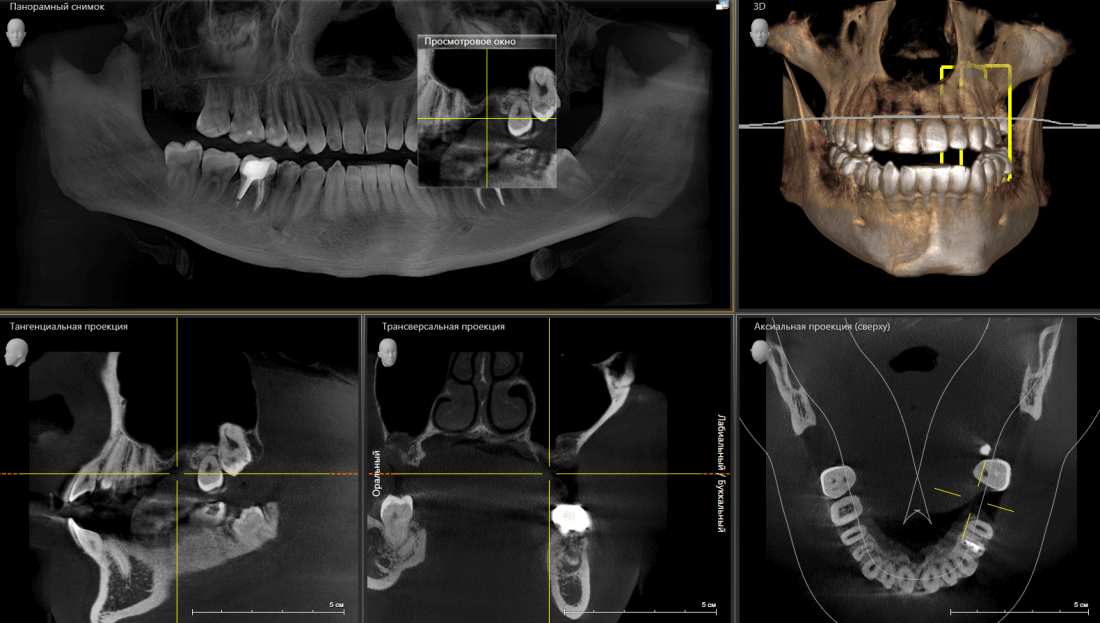

Пациенту удалили 26 зуб около двух месяцев назад. Вот компьютерная томография

Подробнее:

В общем, тут нужен синуслифтинг. И, исходя из последних данных об этой операции, 2,6 мм до дна верхнечелюстной полости достаточно, чтобы нормально стабилизировать имплантат, в т. ч. Astra Tech.

26 зуб удалён относительно недавно, поэтому альвеолярный гребень сохранил ширину — это даст нам возможность поставить бескомпромиссно большой по диаметру имплантат — 5.0 мм.

В этой конкретной клинической ситуации первичная стабильность не зависит от длины имплантата, поэтому длину можно выбирать любую. Мы возьмём оптимальную — 9.0 мм. Ибо проще будет с синуслифтингом.